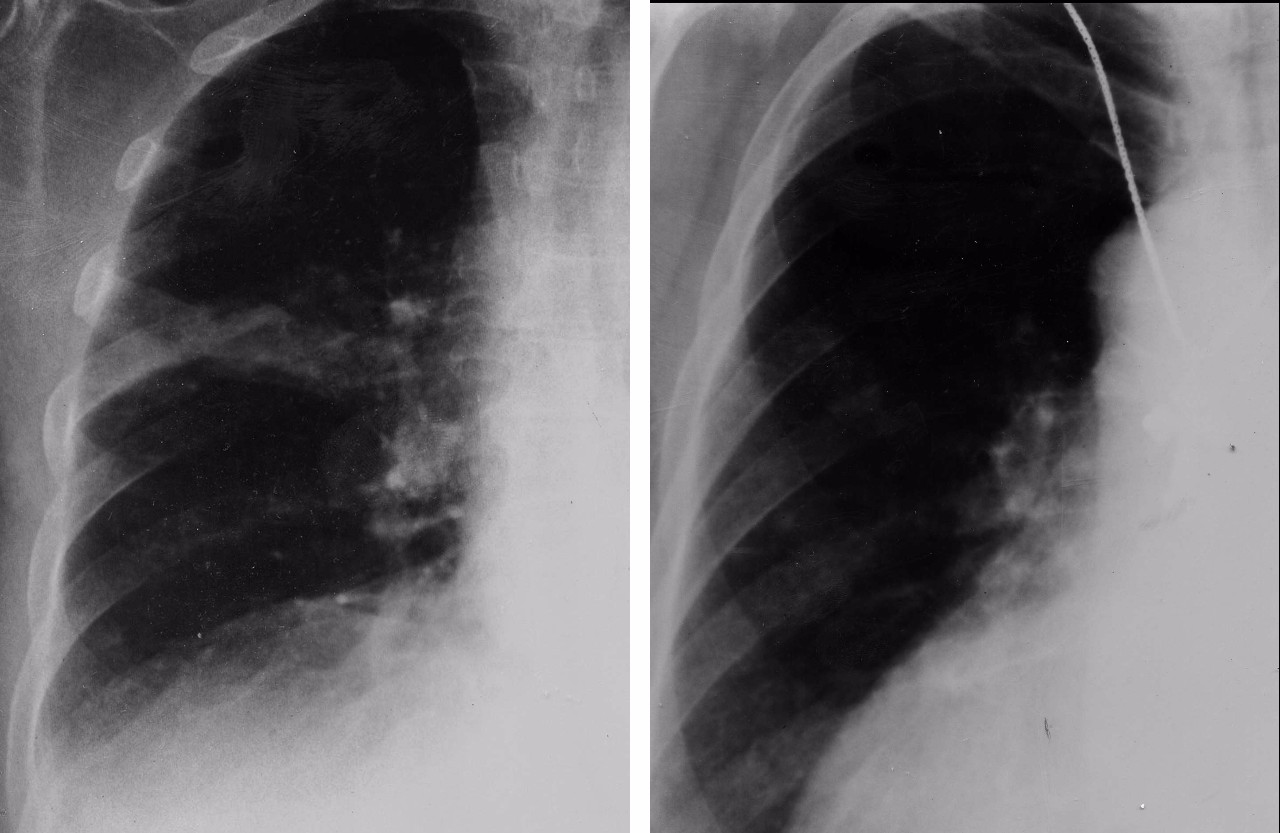

Пневмоторакс и буллезная эмфизема

Пневмоторакс и буллезная эмфизема

Пневмоторакс и буллезная эмфизема

Буллезная эмфизема рентген

Фото рентгеновских снимков поражения легких при COVID-19

На фотографиях рентгеновских снимков видно, как вирус воздействует на легочную ткань. Характерные признаки поражения легких включают пятна, инфильтраты и наличие жидкости внутри легочных альвеол.

Фото рентгеновских снимков помогают врачам и специалистам визуально определить степень поражения легких и принять соответствующие меры лечения и поддержки пациента.